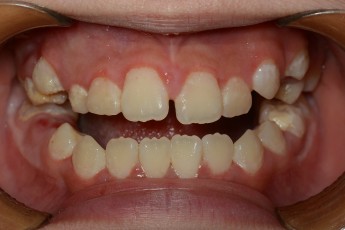

Before

After